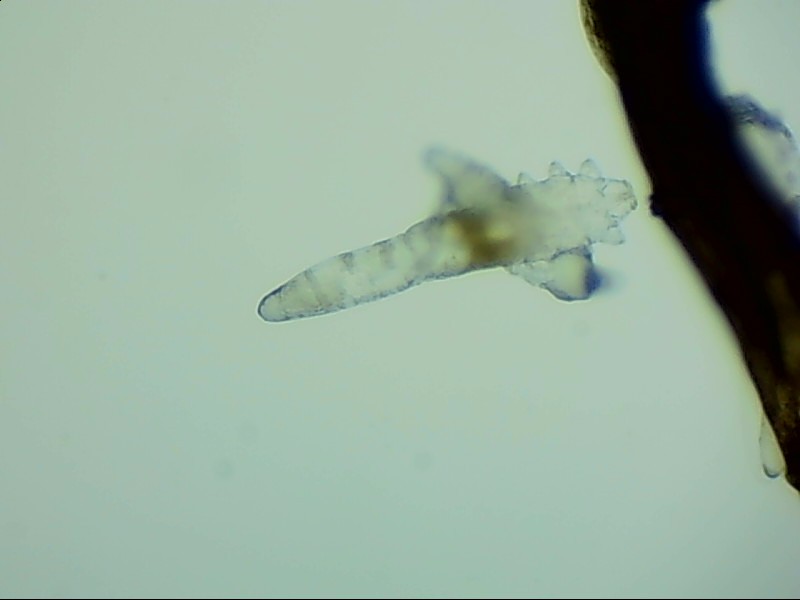

人體上寄生著兩種蠕形螨,分別是毛囊蠕形螨和皮脂蠕形螨,它們以睫毛囊上皮細胞、腺體內(nèi)脂質(zhì)為食物,因此主要寄生在面部、眼睛、頭皮等地方,其中寄生在眼睛里的蠕形螨主要活動在睫毛毛囊、睫毛皮脂腺,以及瞼板腺里。

蠕形螨完全長大也只有0.1-0.2毫米,因此肉眼難以看到它們,只有在電子顯微鏡下我們才能看到睫毛根部的一只只蠕形螨。這些螨蟲每天都很活躍,且繁殖速度極快,完成一代生活史僅需大概15天。

螨蟲鏡檢主要是通過顯微鏡觀察,它能無死角放大你的睫毛,讓螨蟲無處可躲。

在檢查的時候,醫(yī)生要在每個眼瞼上拔出幾根比較典型的睫毛,然后放在光學(xué)顯微鏡下,尋找有沒有螨蟲,同時觀察螨蟲的數(shù)量多少。

如果任意一個眼瞼上螨蟲數(shù)量較多,再加上你的眼睛有局部癥狀,后續(xù)就需要進行相應(yīng)的治療了。